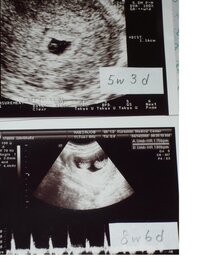

双子だとわかるのはいつ? 病院の検査で双子だとわかるのは 早くて妊娠5週の後半 です! 二卵性の双子の場合は、はじめての受診でわかることがほとんどです! 妊娠を確認するための超音波(エコー)検査で、胎嚢が二つ確認できれば双子だと確定され 無脳症はいつわかる? 先天異常とは、赤ちゃんが生まれつき持っている異常のことです。 ここでは、そんな 先天異常のなかでも、無脳症についてご紹介します。 無脳症とは具体的にどんな異常なのか、妊娠したらどの時期からわかるようになるのか妊娠5週目~7週目でわかる人が半数! 双子妊娠がわかった時の週数も尋ねたところ、 5週目~7週目でわかる人が半数 でした。

双子の妊娠っていつ分かるの? それではいよいよ、双子の妊娠がいつ分かるのか?という事について説明します。結論から言いますと、双子の妊娠は 早い人なら妊娠5週ぐらいで分かります。 半数以上の妊婦の方が、初回の妊婦検診で妊娠が分かっています 双子妊娠発覚! いつわかる? リスクは? まとめ 突然の双子や三つ子ちゃんの判明で動揺された方が多いと思います。 育児は確かに想像通り大変ですが、 やっぱり赤ちゃんが並んでいるところや遊んでるところを見ると癒されるし、可愛さも2倍以上 双子の妊娠発覚はどのタイミングでわかるの? 私の場合は、妊娠5週目で『胎嚢 (たいのう)=赤ちゃんのベッドのようなもの』を見つけました。 1回目の検診では、1つの胎嚢の確認で単胎児